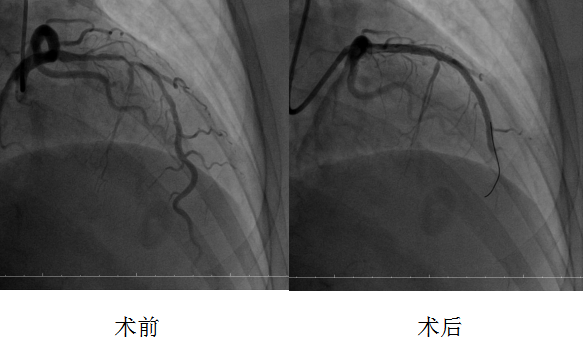

10月17日,在介入科的全力配合下,劉波主任主導(dǎo)開展手術(shù)。手術(shù)團隊運用直徑僅1.5毫米的高速旋磨頭,以每分鐘15萬轉(zhuǎn)的轉(zhuǎn)速精準(zhǔn)“打磨”血管內(nèi)鈣化病灶,三次旋磨成功打通病變通路,隨后順利為患者串聯(lián)植入兩枚藥物支架并以球囊行后擴張。為確保手術(shù)效果,團隊還通過血管內(nèi)超聲檢查精準(zhǔn)評估支架貼壁情況,對支架近端進行補充后擴張。復(fù)查造影顯示,支架釋放滿意,血管狹窄解除,血流恢復(fù)正常。術(shù)后1小時即實施雙泵透析,有效降低造影劑對腎臟的影響,保障了患者心腎功能穩(wěn)定。經(jīng)過后續(xù)規(guī)范治療,患者恢復(fù)良好,現(xiàn)已順利出院。